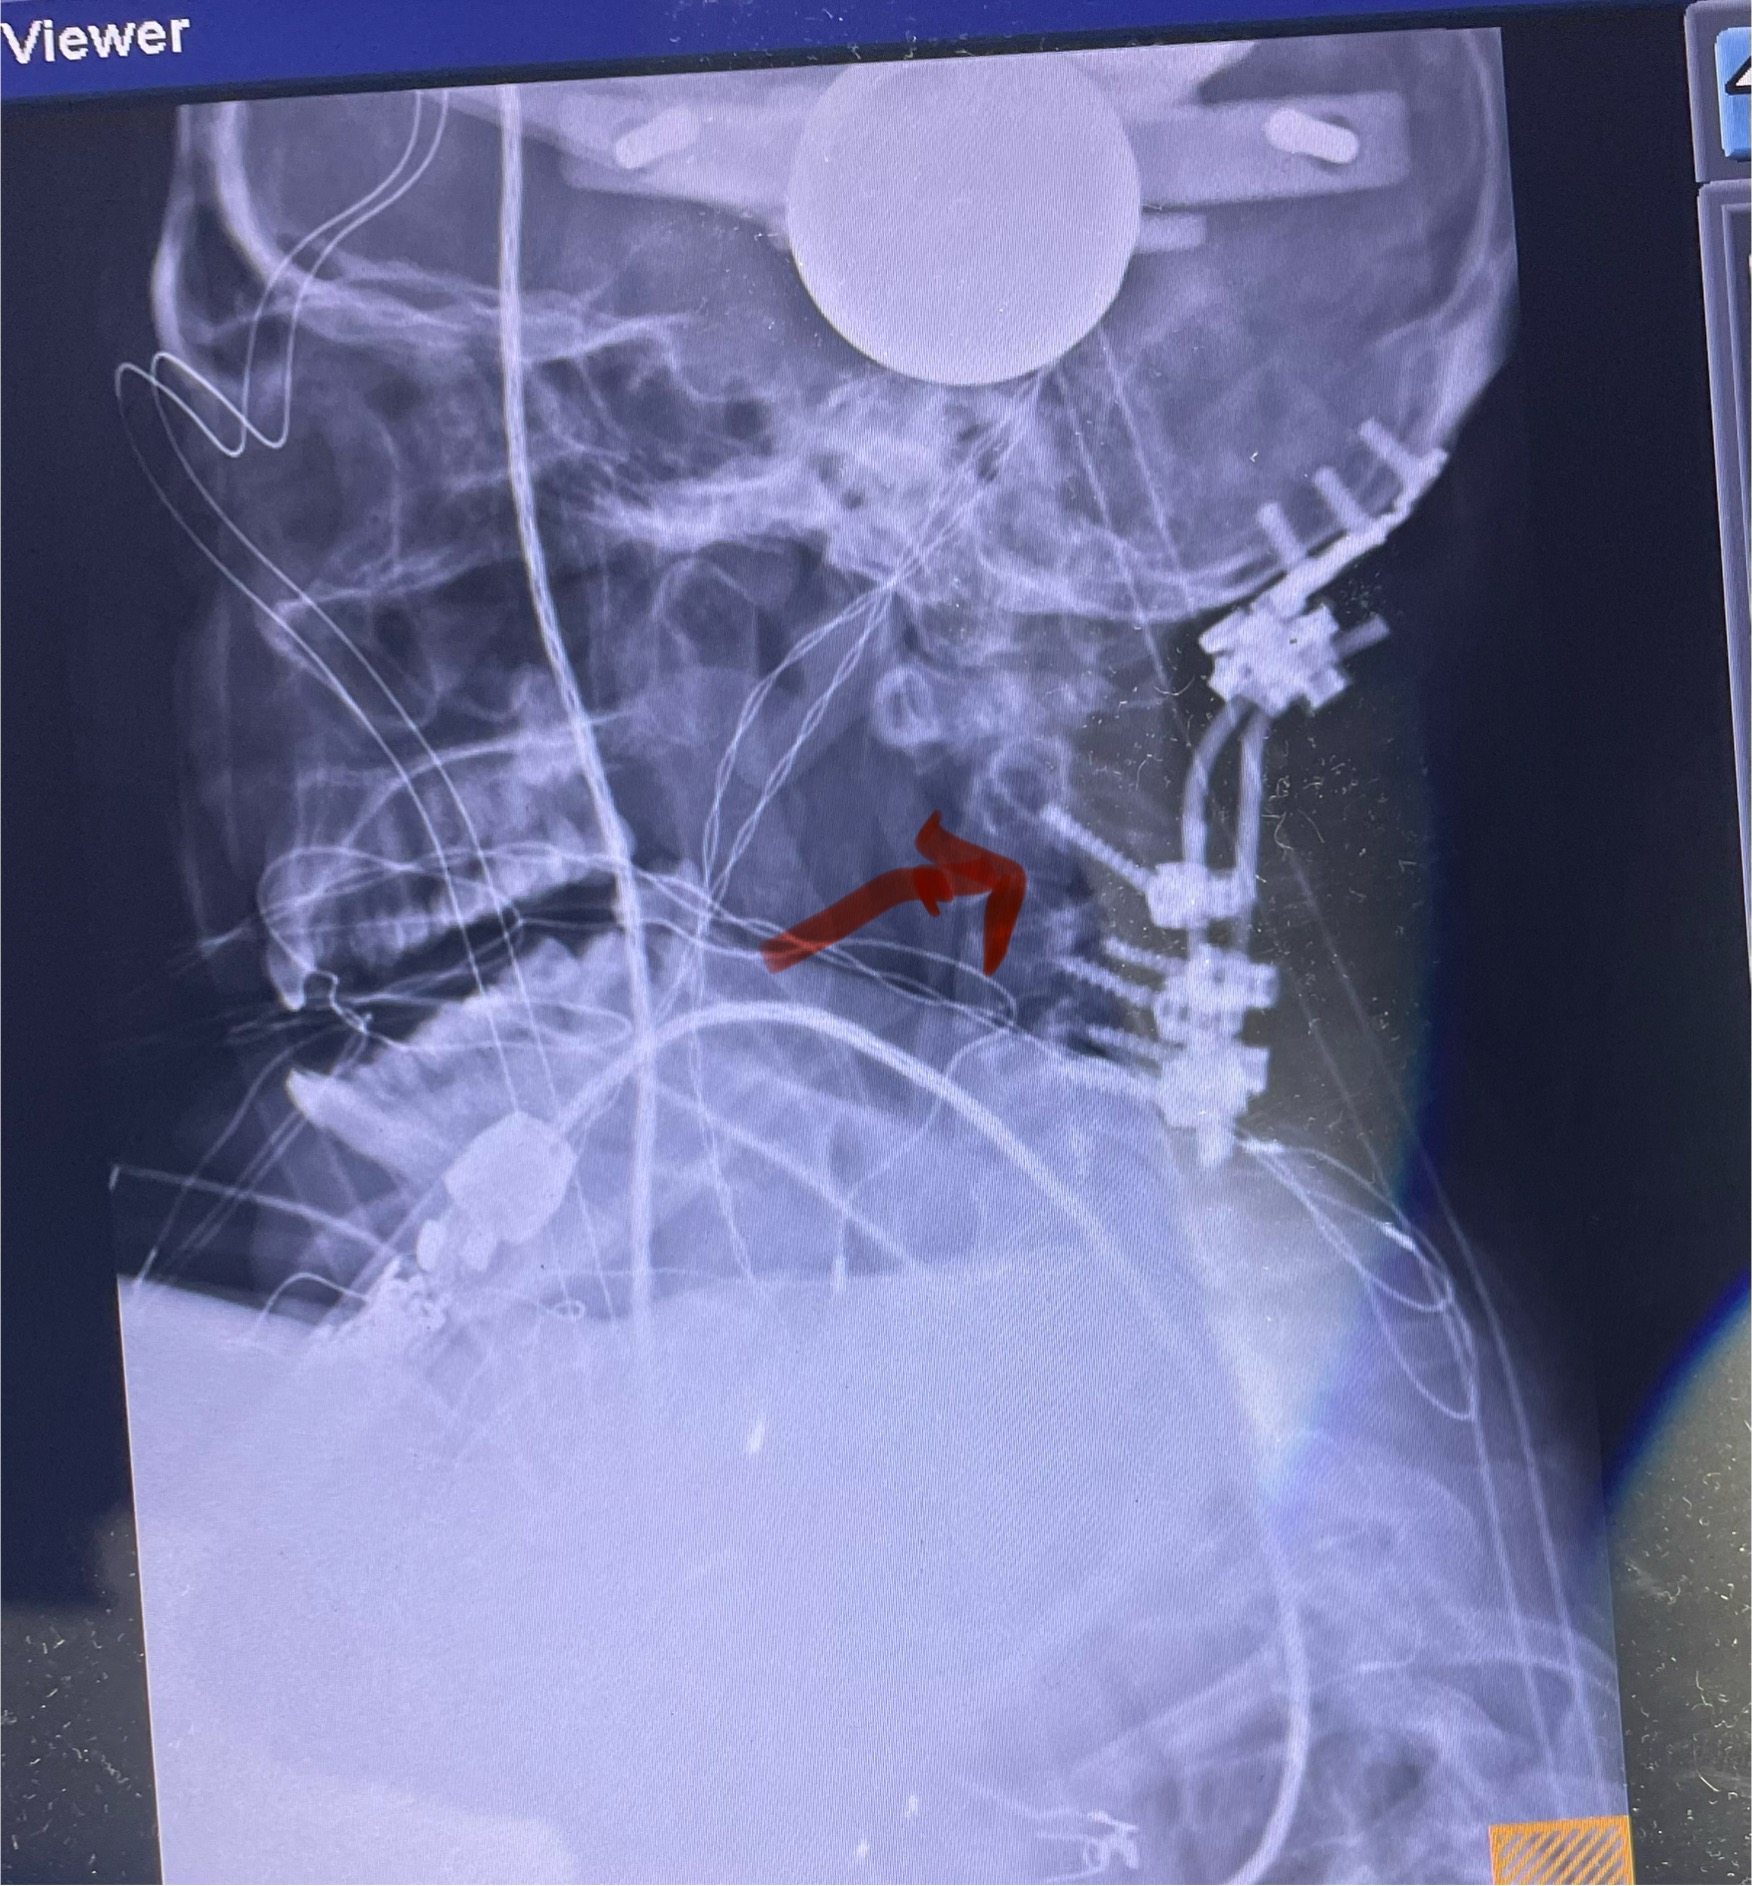

SOMETIMES YOU HAVE TO CONNECT THE SKULL TO THE NECK